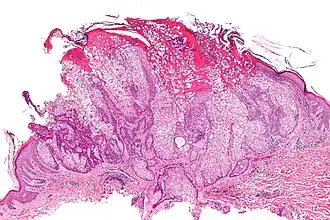

![]() Аденома сальных желёз (гистологический препарат, окраска гематоксилином и эозином) | |

Аденома сальных желёз — доброкачественная опухоль кожи, которая развивается из железистого или протокового эпителия[1] сальных желёз и, как правило, характеризуется медленным ростом. Обычно выглядит как розовая, цвета кожных покровов, либо желтоватая папула или узелок[2][3].